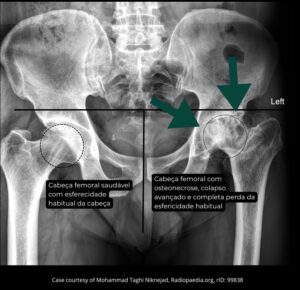

Radiografia anteroposterior (AP) da bacia. Nota-se a esfericidade preservada da cabeça femoral à direita, em contraste com o colapso avançado à esquerda.

Na fase avançada, ocorre perda da esfericidade da cabeça do fêmur, com deformação articular e desenvolvimento de artrose secundária do quadril.